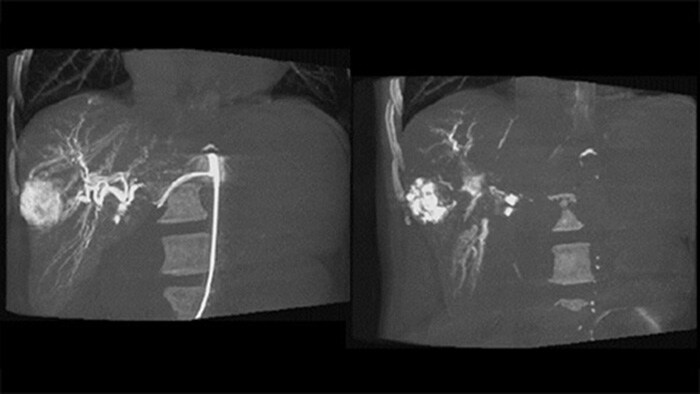

Dual View permite la visualización simultánea de dos conjuntos de datos CBCT. Tanto la fase arterial como la retardada pueden mostrarse una al lado de la otra o en una sola vista de superposición fusionada.

Dual View permite la visualización simultánea de la imagen 3D de fase arterial antes de la embolización y la imagen después de la embolización para evaluar el criterio de valoración del tratamiento.